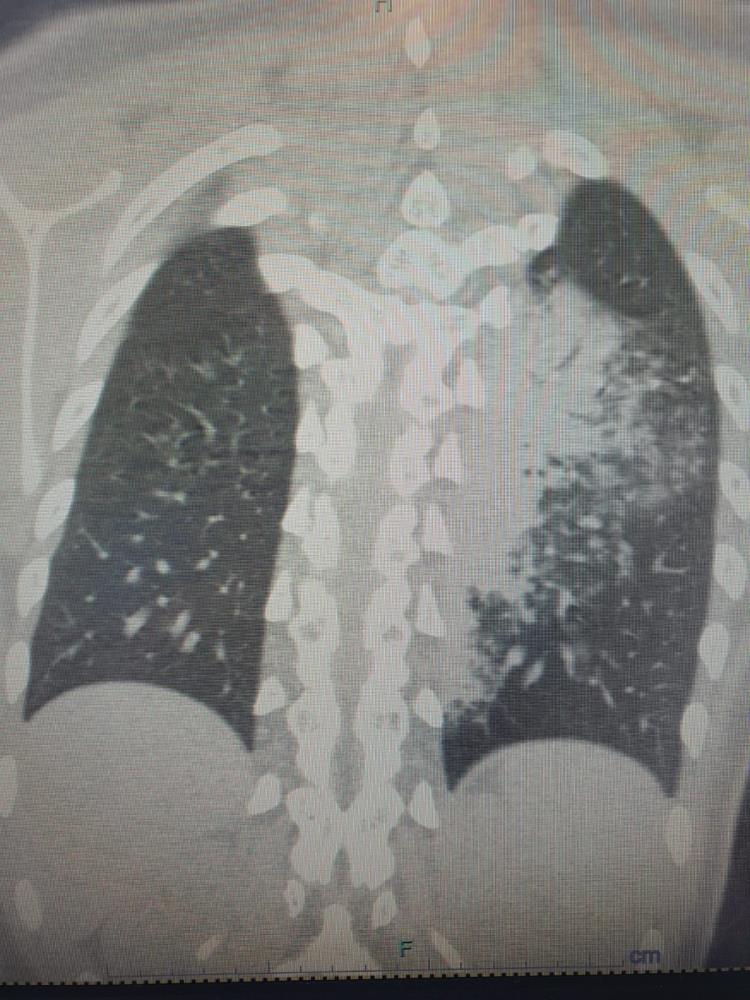

Sıcakların artması ve yaz sezonu ile tatile çıkanların klima kullanımı artarken, bronşit ve zatürre vakaları da hızla yükseliyor. Altınbaş Üniversitesi Tıp Fakültesi Göğüs Hastalıkları Anabilim Dalı Öğretim Üyesi Prof. Dr. Şevket Özkaya, özellikle otel ve tatil köylerinde klima maruziyetine bağlı hastalıkların arttığını ve en çok etkilenenlerin çocuklar olduğunu vurguladı. Prof. Dr. Özkaya, “Legionella” bakterisinin klimalardan üremesi sonucu ortaya çıkan “Lejyoner hastalığı”nın, çocuklarda COVID-19’a oranla daha fazla zatürreye neden olduğunu ve bu durumun şaşırtıcı ve endişe verici olduğunu ifade etti. Prof. Dr. Özkaya, vatandaşların klima kullanımında dikkatli olmaları gerektiğini ve özellikle kronik hastalığı olan kişilerin bu konuda daha duyarlı olması gerektiğini belirtti.

Göğüs Hastalıkları Uzmanı Prof. Dr. Şevket Özkaya, özellikle otel ve tatil köylerinde konaklayan kişiler arasında “beni klima çarptı” diyen neredeyse her iki kişiden birinde bu hastalıkların saptandığını belirtti. Prof. Dr. Özkaya, bu durumdan en çok etkilenenlerin ise çocuk yaş grubu olduğunu vurgulayarak, “Ciddi sayıda, daha önce görülmemiş derecede çocuk bronşiti ve zatürresi vakaları görmeye başladık. Hatta COVID-19 salgınında, çocuk yaş grubunda COVID-19 virüsüne bağlı bu kadar çok zatürre görmüyorduk. Son günlerde; ‘Legionella’ bakterisinin, çocuk yaş grubunda COVID-19’a oranla çok daha fazla zatürreye neden olduğunu görüyoruz” diye konuştu.

Legionella pneumophila isimli bakterinin klimalardan üremesi sonucunda hastalığın ortaya çıktığını belirten Prof. Dr. Özkaya, bu hastalığın kronik rahatsızlığı olanlarda ölümcül olabileceğini ve yaşlı, kronik hastalığı olan vatandaşların dikkatli olmaları gerektiğini hatırlattı.

Özellikle klimaların iyi temizlenmesi gerektiğini belirten Prof. Dr. Özkaya, klima zatürresinde şikayetlerin daha az olduğu için grip gibi eklem ağrıları, ateş, halsizlik, ishal gibi hafif soğuk algınlığı belirtileriyle seyrettiği için çok fazla anlaşılmayabileceğini söyledi. Kronik hastalığı olanlarda hayati sonuçlar da doğurabileceğini belirten Özkaya, “Pandeminin bitmesiyle beraber ani ısı değişikliklerine, soğuktan sıcağa geçişlere ve klimalara maruz kalmak, grip ile karıştırılabilir ve önemsenmeyebilir. Çocuklar ise ne hissettiklerini anlatamadıkları için uzamış öksürük ve ateş şikayeti ile doktora başvurduklarında ciddi zatürre vakaları ile karşı karşıya kalırlar” dedi.